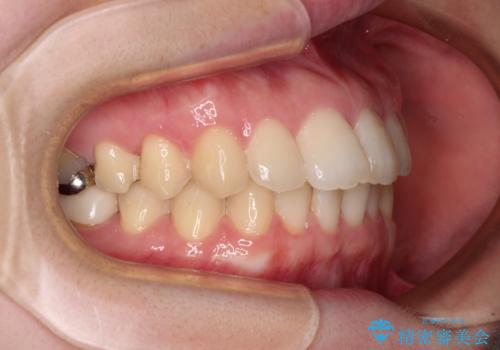

デコボコ歯列をきれいに インビザラインによる矯正治療

- 上下歯列全体のデコボコを気にして来院された患者様です。

主に下顎歯列全体の後方移動とIPR(歯と歯の間を削る)によってデコボコが解消するように設計し、インビザラインにより治療を行うこととしました。

1年半程度で終了するのではないかと予想しましたが、途中1年以上の来院がなく、トータルで3年の時間がかかってしまいました。

前歯のデコボコはより改善することが望ましい状態でしたが、患者様の希望により終了することとなりました。